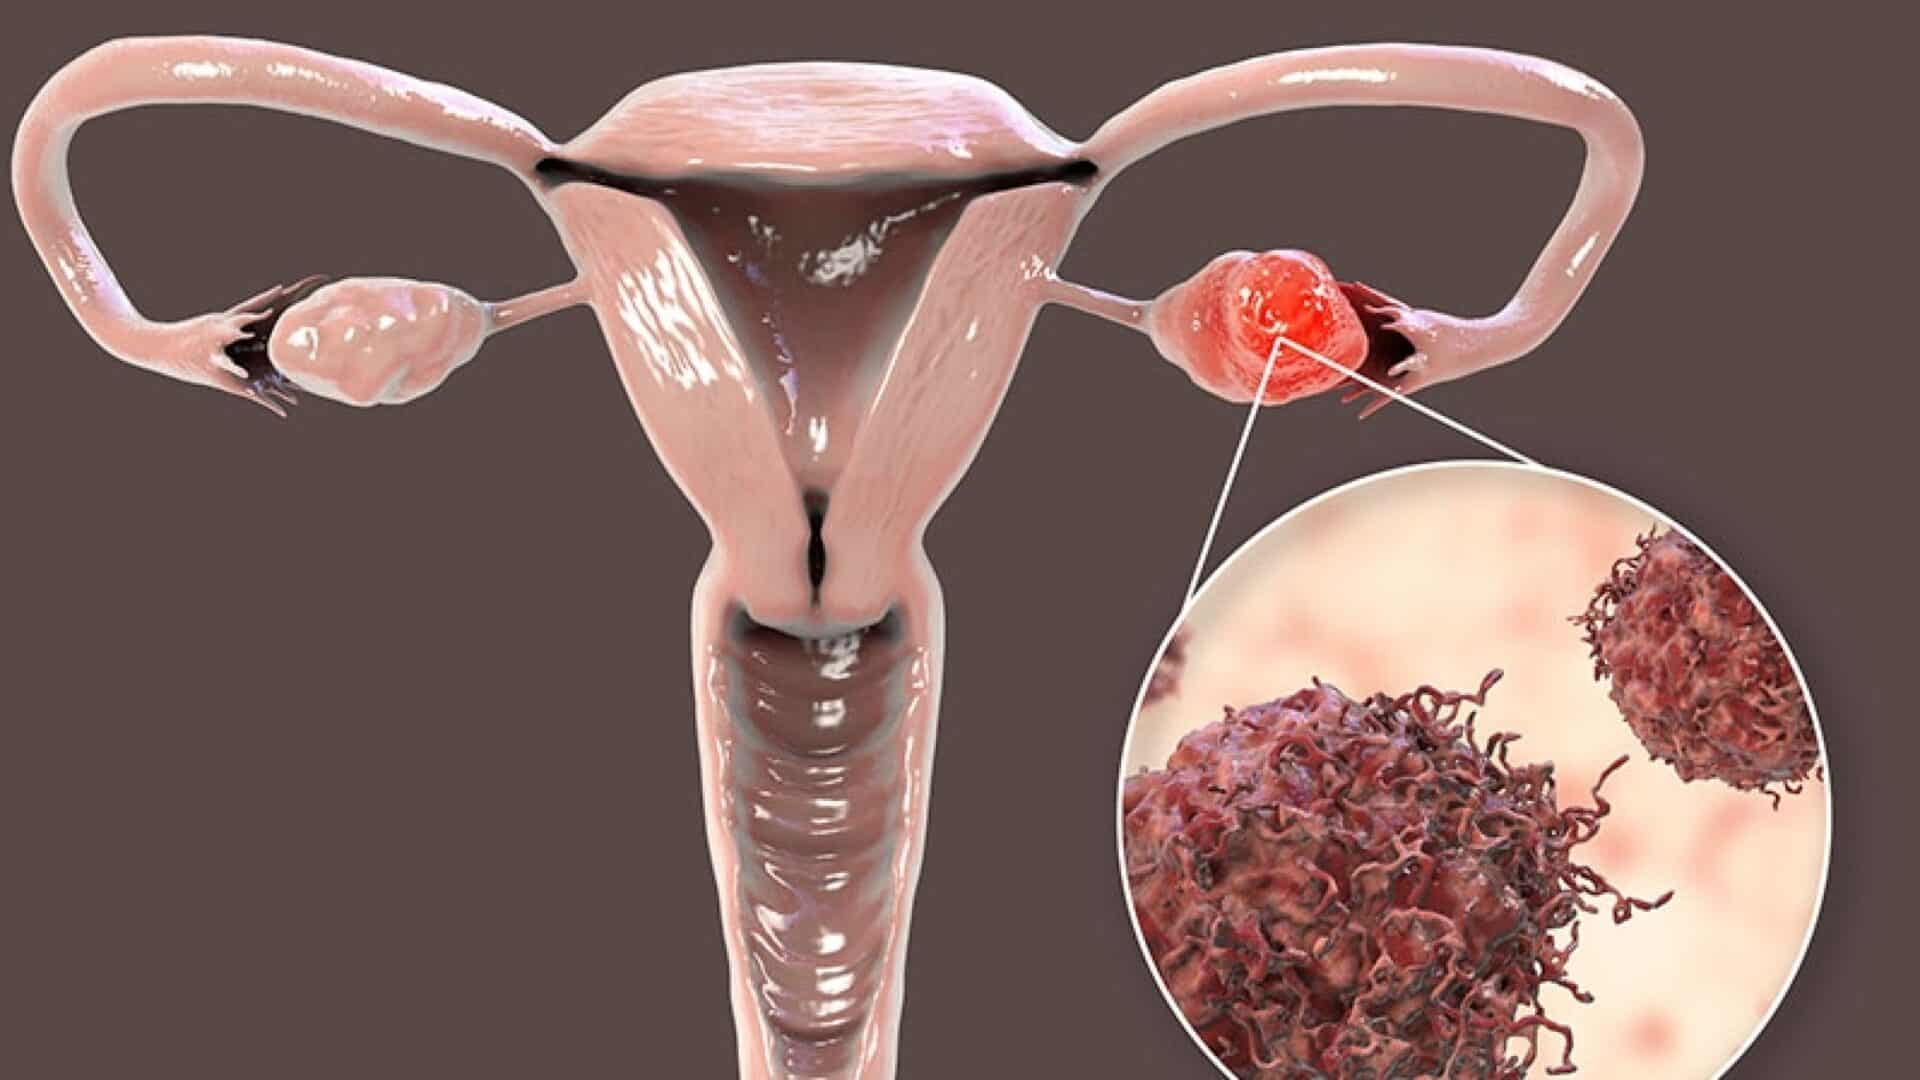

Συμπτώματα καρκίνου των ωοθηκών

Μία από τις σημαντικότερες συνδέσεις μεταξύ του καρκίνου των ωοθηκών και του καρκίνου του μαστού είναι οι μεταλλάξεις στα γονίδια BRCA1 και BRCA2. Κανονικά, αυτά τα γονίδια βοηθούν στην επιδιόρθωση του κατεστραμμένου DNA και εμποδίζουν την ανάπτυξη όγκων. Ωστόσο, οι μεταλλάξεις στο BRCA1 ή BRCA2 αυξάνουν σημαντικά τον κίνδυνο εμφάνισης καρκίνου του μαστού και των ωοθηκών.

Η έγκαιρη διάγνωση είναι καθοριστική για την επιτυχή θεραπεία. Ο καρκίνος των ωοθηκών ιδιαίτερα συχνά διαγιγνώσκεται αργά λόγω ασαφών συμπτωμάτων, γι’ αυτό είναι σημαντική η γνώση του προσωπικού και οικογενειακού κινδύνου σας.

Οι μεταλλάξεις στα γονίδια BRCA1 και BRCA2 αυξάνουν σημαντικά τον κίνδυνο για καρκίνο του μαστού και των ωοθηκών.